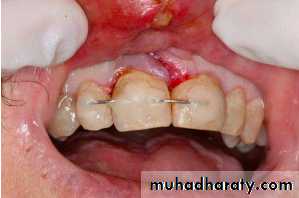

Associated injuries-Fracture of alveolar socket wall

- Injuries to the lips and gingiva